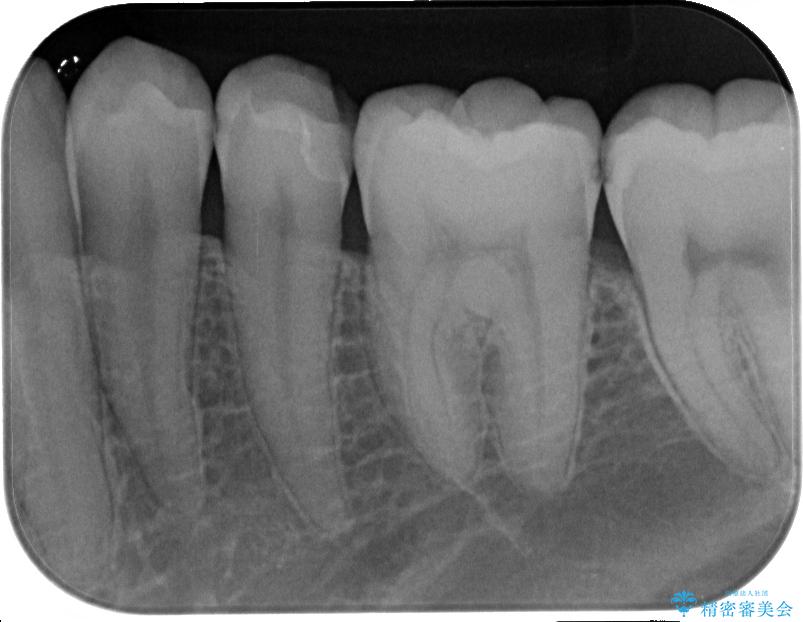

- 左下の奥歯のところがフロスが引っかかったり、ちぎれたりするとのことで来院された患者様です。検査の結果、神経は正常な反応を示し、フロスは引っかかる状態でしたので、虫歯治療も併せて行うためにオールセラミッククラウンによる補綴治療を行っていくことにしました。

拡大鏡視野下でプラスチックの詰め物、虫歯を除去しオールセラミッククラウンに適した形に整えました。